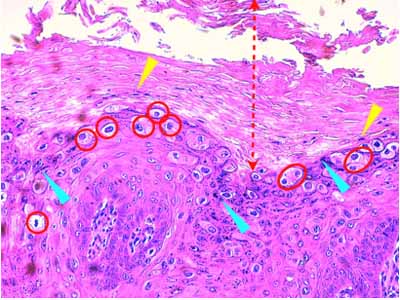

A l’examen histologique, on observe des néoformations verruqueuses, exophytiques, constituées d’un épiderme bien différencié, sévèrement hyperplasique, produisant à la surface du tégument, des projections digitées, longues et étroites (Fig 2). Cet épiderme est le siège d’une sévère hyperkératose orthokératosique ou parakératosique et d’une hypergranulose avec de volumineux grains de kératohyaline (Fig 3 &6). Sa couche basale est très développée, cellulaire, mitotique, hyperbasophile (Fig 4 & 5). Les acanthocytes sous-cornés sont vacuolisés (Fig 3 & 7). Ils montrent un cytoplasme bleuté, discrètement fibrillaire (Fig 6), ou vacuolisé, leur noyau parfois pycnotique étant entouré d’un halo clair. Il s’agit de koïlocytes (Fig 7). Certains montrent un noyau avec margination chromatinienne laissant un centre bleuté compatible avec une inclusion basophile (Fig 7). Dans le derme papillaire sous-jacent, on observe un infiltrat inflammatoire lympho-plasmocytaire d’intensité modérée. Absence d’image suspecte de malignité.

Photo 3 (Hémalun Eosine X 200) : L’épiderme hyperplasique émet des papilles coniques,

au sommet desquelles la couche cornée est très épaisse et (sur cette vue) parakératosique.

La couche granuleuse renferme de volumineux grains de kératohyaline.

Les acanthocytes sous-cornés sont vauolisés (koïlocytose).

Légendes de la Photo 3 :

- Double flèche pointillée rouge : couche cornée épaissie

- Pointe de flèche jaune : noyau résiduel de cornéocyte dans la couche cornée. La couche cornée est parakératosique

- Pointes de flèche turquoises : nombreux et volumineux grains de kératohyaline signant une hypergranulose de la couche des grains (stratum granulosum)

- Cercles rouges : koïlocytes : kératinocytes présentant un noyau entouré d’un halo clair